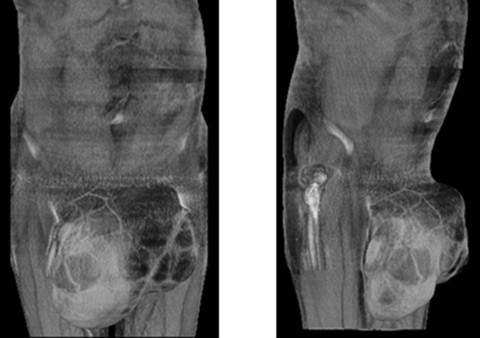

| Khối u tự do được chụp lại bên trong cơ thể bệnh nhân. |

Tờ New England Journal of Medicine tiết lộ các bước chụp CT scan bụng đã phát hiện một khối u khổng lồ có hình dạng như quả trứng luộc đè lên bàng quang ông này. Sau đó, các bác sĩ đã tiến hành đưa camera vào thăm dò bên trong ổ bụng ông này, họ phát hiện khối u này "trôi nổi tự do, mịn màng và săn chắc như một cục cao su". Khối u kỳ lạ này có kích thước đáng kinh ngạc với chiều dài 10cm và rộng 7,5cm, nặng 220g tương đương với một quả cam lớn.